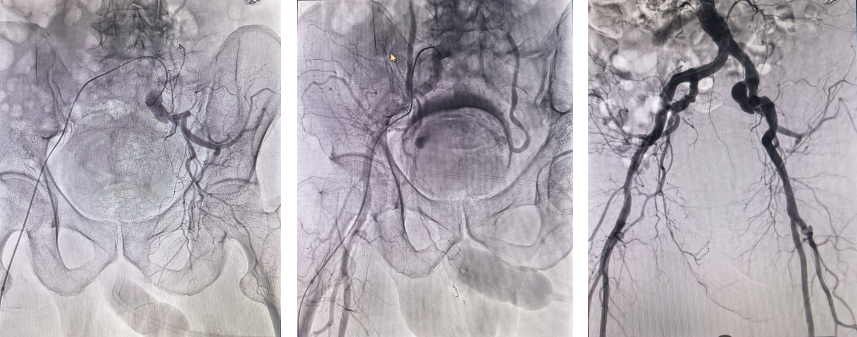

怎么办?需要紧急止血、紧急清理膀胱血凝块。但是,患者颅内支架术后需要抗栓,不能全身用抗凝药,而膀胱内大量出血急需止血,局部止血无效;膀胱过度充盈,患者疼痛难忍,而外科手术存在术中难于止血的风险,治疗存在两难。张桂莲主任医师在和泌尿外科主任医师种铁院长电话沟通后,在泌尿外科主任薛力及影像科介入团队刘强副主任医师、彭玉萍主任医师的鼎力支持下,神内李雯娴医生、郝志国护士快速将患者送到导管室,决定尽快进行盆腔血管造影寻找出血动脉,必要时进行出血动脉栓塞止血,同时快速清理过度充盈的膀胱内积血。髂动脉造影由影像科杨晓东和李健鹏完成,膀胱内积血由泌尿外科副主任薛玉泉完成,经过2小时的紧张抢救,患者病情快速好转,出血停止,腹痛腹胀消失,生命体征快速恢复稳定,腹部CT及泌尿系统彩超见膀胱内血凝块消失,膀胱填塞危机得以解除。

左侧髂动脉 右侧髂动脉 双侧髂动脉及其分支